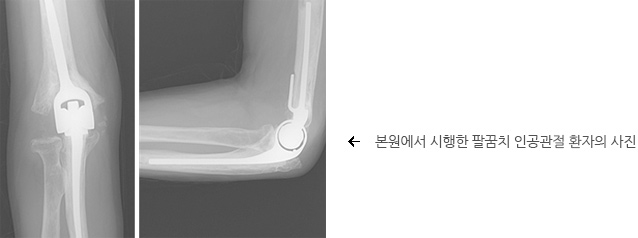

진행된 관절염으로 통증이 지속되거나 척골 신경 증상이 현저하게 나타나면 수술적 치료를 시행하는 것이 필요합니다. 특히 골극의 생성, 관절안유리체 등으로 인한 물리적인 충돌로 인한 통증인 경우는 수술적으로 이들을 제거해주는 것이 필요합니다. 수술 전 척골 신경병증이 동반된 경우 신경 감압술이나 이전술을 동시에 시행하면 손저림이나 손가락 근력약화 증상의 호전도 기대 할 수 있습니다. 하지만 척골 신경 병변이 오래되고 심할 경우에는 수술 후에도 증상의 호전이 미약할 수 있으므로 조기 진단과 치료가 매우 중요합니다. 수술 후 재활로서는 관절운동이나 일상생활은 바로 시작 할 수 있으며, 특히 관절경 수술은 회복이 빠르며 근육이나 힘줄의 손상 없이 관절 안 병변을 제거할 수 있어 조기에 일상 생활에 복귀할 수 있는 장점이 있습니다. 관절 변형이 심한 경우에는 인공 관절을 이용해서 수술을 시행하기도 합니다.